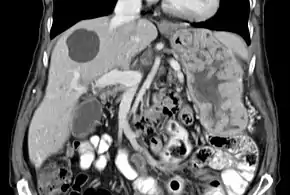

![]() | |

| Biopsy of the stomach in Ménétrier disease showing the substantial pit hyperplasia makes the large rugal folds appear to be covered by myriad polyps resembling hyperplastic polyps. The muscularis propria is the folded structure at the bottom center. | |